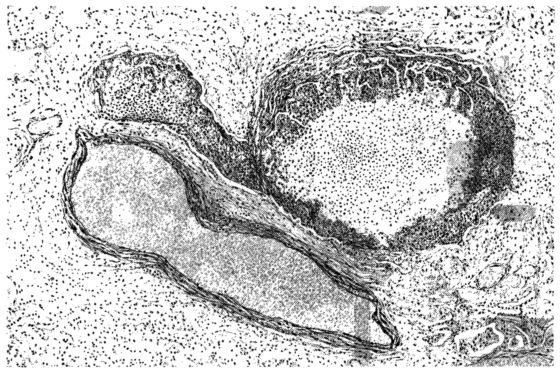

FIG. I. AUTOPSY NO. 99. ACUTE HEMORRHAGIC AND ULCERATIVE LARYNGOTRACHEITIS.

FIG. I. AUTOPSY NO. 99. ACUTE HEMORRHAGIC AND ULCERATIVE LARYNGOTRACHEITIS.

Early in the disease the congestion and the hemorrhages that have been described in the mucous membrane of the nasopharynx (14 and 94) are also conspicuous features in the lining of the trachea and bronchi (Fig. I). This membrane is swollen, turgid, red, and covered by a copious, mucous exudate which may be clear, but much more frequently is blood-stained or opaque and yellowish in color. The blood, variable in amount, may be fresh and red; and after the mucous exudate on the surface is removed, more intense red foci stand out on the congested base (47, 90, 157). Frequently, as the bronchi are approached, the red color of the mucosa becomes more intense and may have a garnet tinge. Membranes such as are encountered in the more usual necrotizing inflammatory processes, like diphtheria, have not occurred in the trachea and larger bronchi in this series (108, 128, 157).[3] The exudate peels off readily, and as indicated above, leaves a velvety red surface, 14dotted here and there with darker or more intensely red foci. Small ulcerations of the mucosa occur, but are inconspicuous (82, 156). As the finer ramifications of the bronchi are approached, the accumulation of the exudate in their lumina becomes more and more marked, and on cross section of the lung, they often stand out conspicuously on account of their increased size and projecting, seromucous, blood-stained content (101, 149, 162).